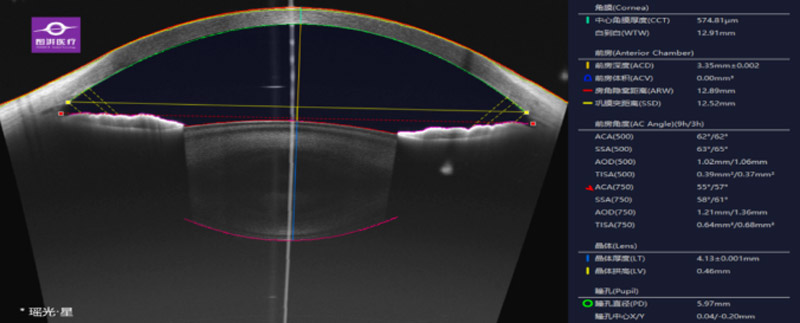

扫频源OCT(SS-OCT),是一种利用弱相干光干涉仪原理实现的生物组织断层扫描成像技术。检查过程仅需数秒钟,具有无损伤、无辐射、非接触等优点,眼部OCT检查具有无创,无辐射且不与人体发生接触的优点,成人、青少年及孕妇都可以放心使用。是目前最前沿的眼科影像学诊断技术之一。

相较于传统频域OCT,新引进的全域扫频,OCT 10万次/秒的扫描速度能大幅缩短检查时间,患者更舒适;波长达1060nm,穿透力更强,对白内障等屈光间质混患者的检出率更高。此外,与传统频域OCT相比,全域扫频OCT成像更清晰、成像范围更广,能够对眼底后极部中周部、全景前节清晰成像,提高诊断准确性。独家脉络膜中大血管OCTA全球独家算法,重现真实的脉络膜血管影像;支持自动或手动测量脉络膜厚度;支持脉络膜毛细血管血流、脉络膜中大血管血流自动识别与成像;独家专利脉络膜中大血管层算法,排除视网膜血管伪影,三维血流定量分析更加客观;提供三维图像特殊分析模式,视网膜十层结构加脉络膜结构逐层独立矢状面影像。